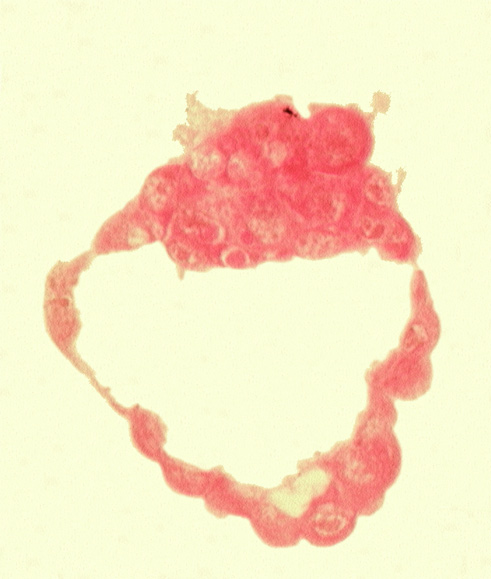

0 μm

Carnegie Embryo #8663 | Location: 01-01-13

Keywords: abembryonic pole, blastocystic cavity (blastocoele), embryonic pole, epiblast, hypoblast, inner cell mass (embryoblast), mural trophoblast, polar trophoblast

Source: The Virtual Human Embryo.